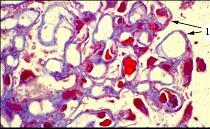

图-1可见上皮下少量嗜复红蛋白沉积(1)(Masson),图-2可见上皮下少量电子致密物沉积沉积(D),上皮细胞足突融合,其病理可诊断为 ( )A...

问题 图-1可见上皮下少量嗜复红蛋白沉积(1)(Masson),图-2可见上皮下少量电子致密物沉积沉积(D),上皮细胞足突融合,其病理可诊断为 ( )

选项 A.Ⅰ期膜性肾病 B.Ⅱ期膜性肾病 C.Ⅲ期膜性肾病 D.Ⅳ期膜性肾病 E.Ⅴ期膜性肾病

答案 A